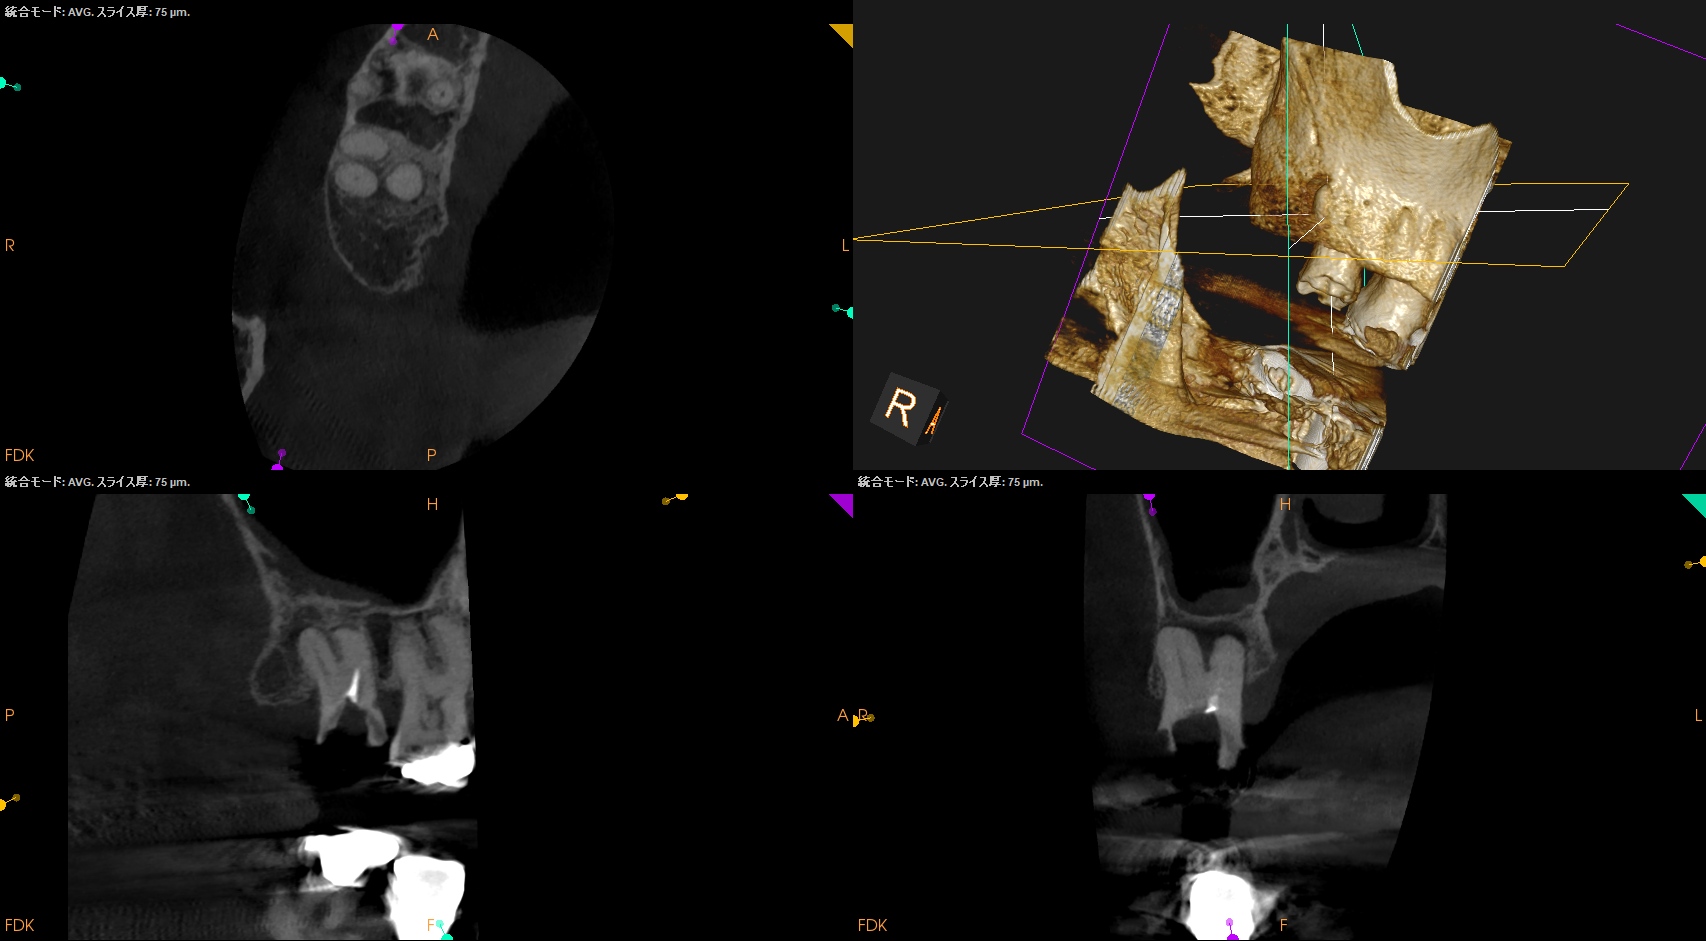

根尖病変があり頬側歯槽骨が穿孔しているDB, レンツロが破断しており根尖病変があるPをSelectiveに再根管治療するという方針を術前に決定した。

#2 Re-RCT(2026.3.9)

それの除去に没頭?すると時間を取られるのでまずはDBからだ。

が、根管口がどの辺りに存在するか?判然としない。

そこでMBのGutta Percha Pointを目印にDBを探索することにした。

SXで上部を拡大した後に根管形成した。

その後、Pだ。

レンツロは以下のようにして除去した。

全長8mmのレンツロは除去された。

まさに秒殺だ。

その後、以下のように形成した。

根管充填後にPA, CBCTを撮影した。

DB

P

問題はないだろう。